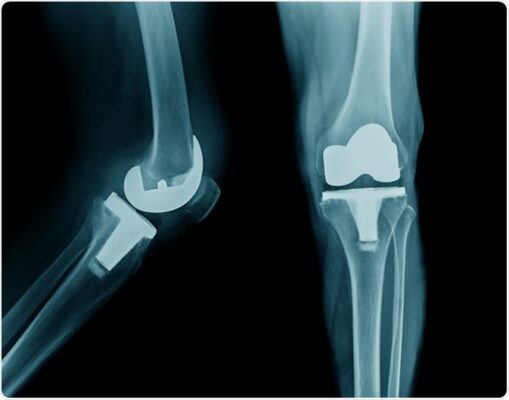

5. Cho ví dụ về các loại khớp gối giả khác nhau (Hình 1).

- Một phần và toàn phần:

- Khớp giả một khoang (Uni-compartmental prosthesis) – dùng để thay thế khoang trong hoặc khoang ngoài của khớp gối khi khoang còn lại còn tốt. Thường là khoang trong, ở người trẻ tuổi, hoạt động.

- Khớp gối giả toàn phần (Total knee prostheses) – là loại thay khớp phổ biến, thay thế cả khoang trong và khoang ngoài và thường cả khớp bánh chè đùi (ba khoang, tricompartmental)

- Mức độ hạn chế (constraint)

- Khớp giả không hạn chế (Unconstrained prostheses) – phục hồi bề mặt khớp, không góp phần vào sự ổn định của khớp. Thường sử dụng nhất; mô mềm nâng đỡ của bệnh nhân giúp giữ ổn định khớp và được sử dụng khi dây chằng còn nguyên vẹn

- Khớp giả bán hạn chế (Semi-constrained prostheses) – góp phần vào sự ổn định của khớp thông qua hình dạng của bộ phận giả và thay thế toàn bộ mặt khớp và xương bánh chè.

- Khớp giả hạn chế hoàn toàn (Fully constrained prostheses) – sử dụng một cơ chế bản lề để tạo sự ổn định cơ học cho khớp. Loại khớp giả này rất khó thay thế trong các trường hợp nhiễm trùng hoặc lỏng lẻo (Dandy & Edwards 2003).

Hầu hết thiết kế sử dụng xi măng polymethylmethacrylate (PMMA) để cố định.

Hình 2: Các loại thay toàn bộ khớp gối. (A) Một khoang (unicompartmental). (B) TKR không hạn chế (unconstrained). (C) TKR có hạn chế (constrained). from Atkinson K et al (2005)